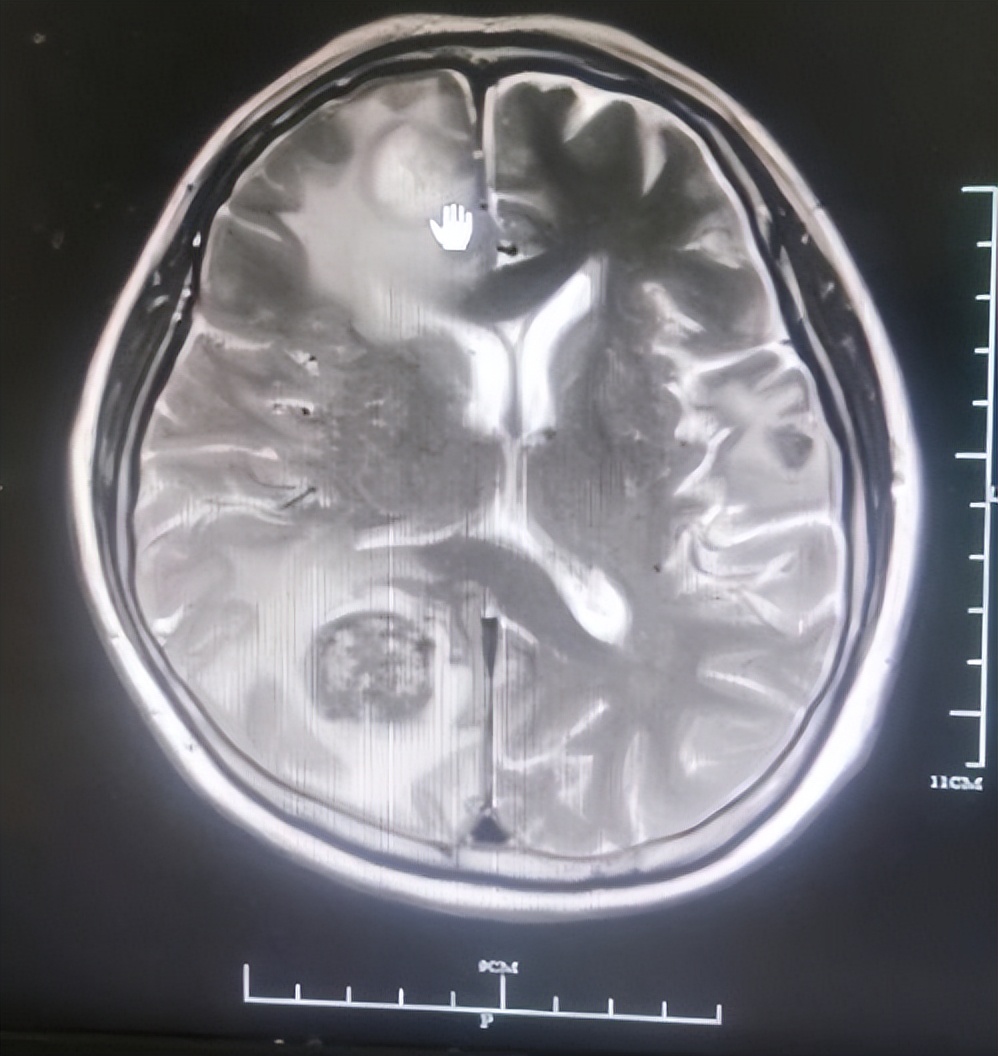

田女士是一位直肠癌患者,有58岁了,已经查出来了晚期,出现了多处转移,一直在外院接受治疗。在2021年7月28日,田女士发现左侧肢体动弹不了,还出现了头晕头痛的情况,接着在外院查了头颅CT后,显示:右额顶叶、左额叶占位,考虑田女士病灶出现了脑转移,又查了头颅MRI,发现颅内有数枚大小不一的结节,右侧枕叶有一稍大一枚结节,长径约3.0cm,提示疾病出现了进展,于是田女士的家属跟外院人员商量好,考虑将田女士转入我院进行下一步治疗。

图为田女士头颅MRI情况

收治入院后,田女士的家属把田女士的片子拿给了我,我看了一下,CT显示:双肺多发结节,肺主动脉窗多发淋巴结,胸8椎体骨质异常密度。分期为TxNxM1 IV期。考虑到田女士出现了脑转移的情况,头晕头痛,左侧肢体活动受限,建议他们先进行放疗来缓解一下目前的情况,田女士的家属表示:大夫,都听你的,只要她的病情能控制住就好啊!于是于2021年8月4日对田女士颅脑转移瘤进行姑息减症放疗15次,靶区包括全脑,经放疗后,田女士的左肢有了明显改善,可以正常活动。